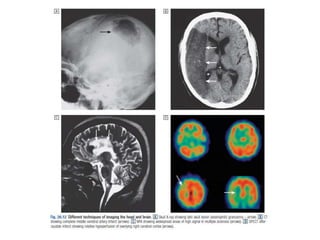

Modalities

• X-Ray

CXR

Plain abdominal x-ray

• Computed tomography

• Magnetic resonance

imaging

• Ultrasound

• Nuclear imaging